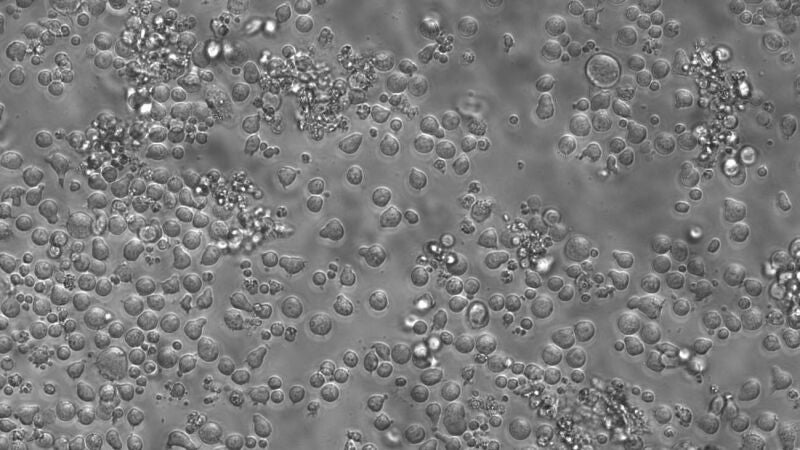

El envejecimiento se produce cuando un solo tipo de células madre supera a sus vecinas y toma el control de la producción de sangre en la médula ósea, según explica el estudio.

En concreto, proliferan un tipo concreto de células mieloides que se relacionan con afecciones como la inflamación crónica, que es un factor de riesgo de enfermedades cardiovasculares y leucemia.

La expansión de estas células inicia la aparición de patologías de la sangre y otras inmunológicas en adultos de edad avanzada, según advierte Rodríguez- Fraticelli. "Una gran parte de los que estamos aquí, sufriremos alguna de estas enfermedades en algún punto de nuestra vida", sugiere el científico, aunque el proceso de envejecimiento de la sangre empieza a los 50.

"Cuando tengamos 60 años, esta familia celular ya habrá expandido por toda la médula ósea y generará trillones de células de este tipo en la sangre todos los días", señala.